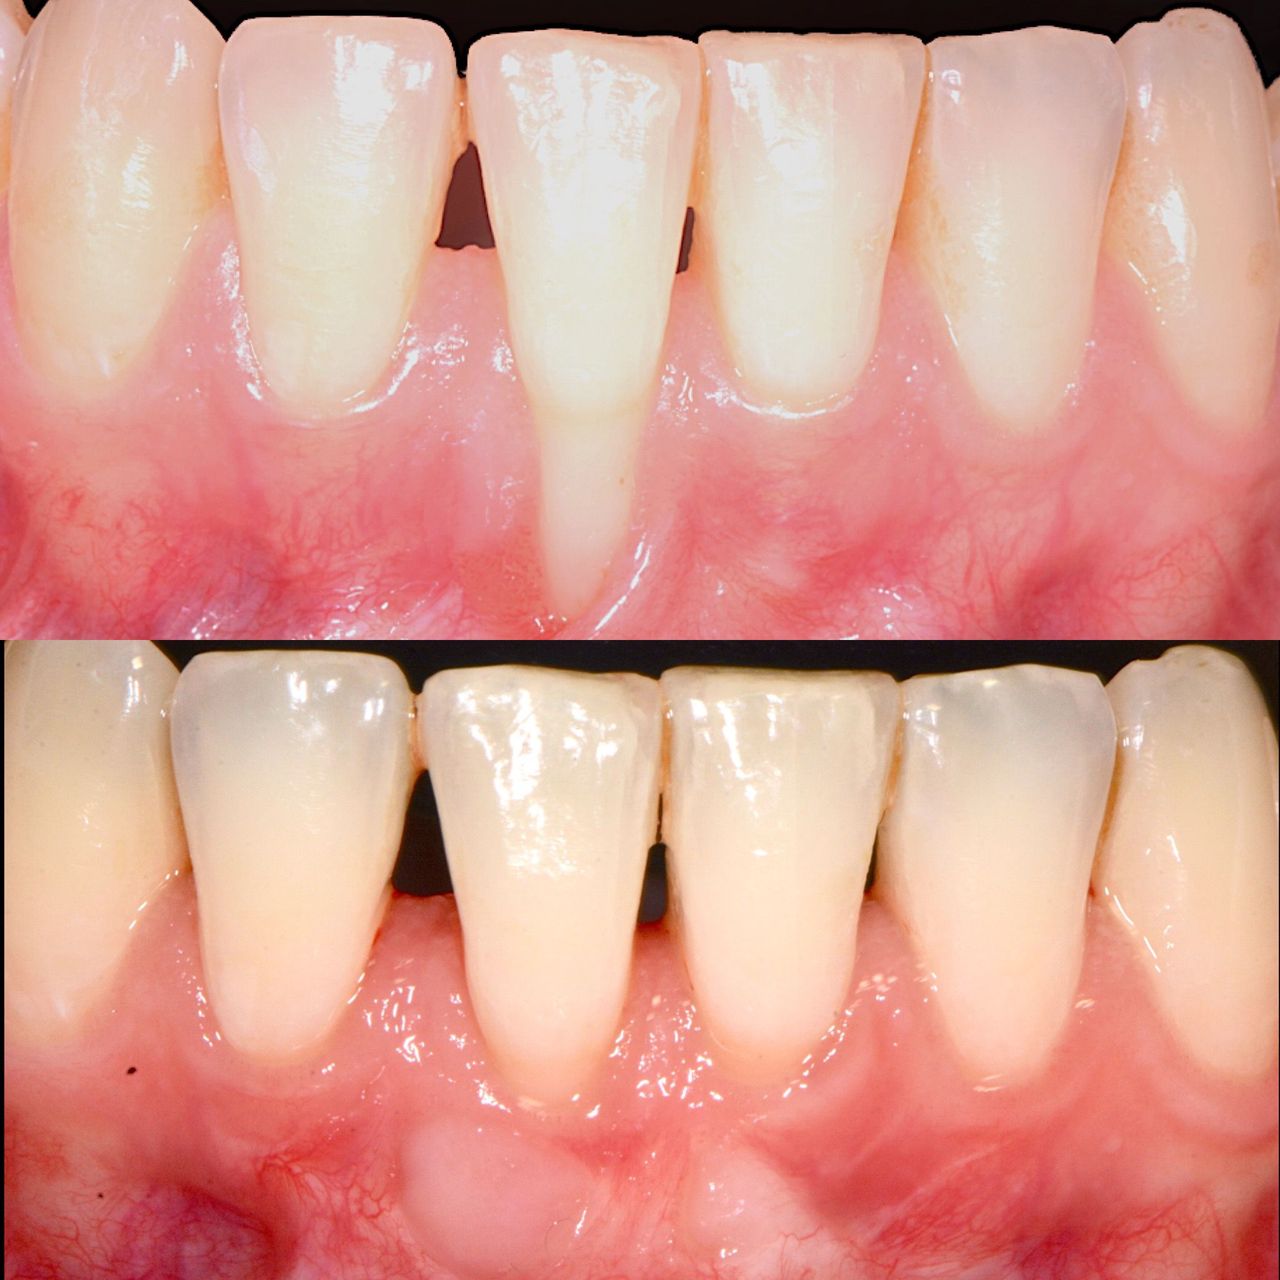

Foto e video